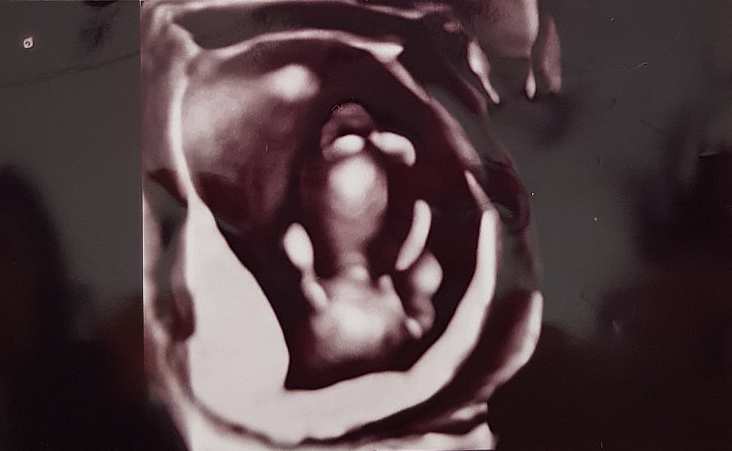

임신준비 여자 흑염소진액 효과 추천 후기

소정의 고료를 지급받고 작성한 후기입니다. 결혼하고 나서 자연스럽게 임신 준비를 시작했어요. 사실 처음...